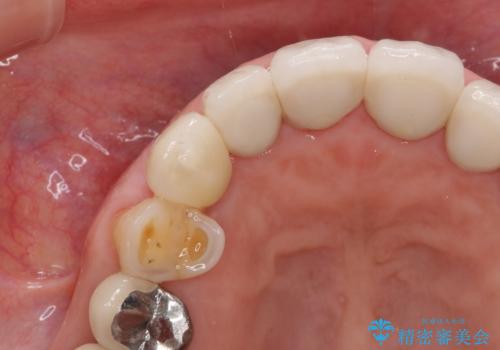

クラウン下に再発した深い虫歯 インプラントによる機能回復

- 定期検診で通院されていたところ、20年前に他院で治療した前歯のセラミック歯の下に深い虫歯が再発していることがわかりました。

ブリッジや歯の挺出を行い保存する提案も行いましたが、短期間の定期的な通院が難しくインプラントによる少ない回数での治療を希望されました。